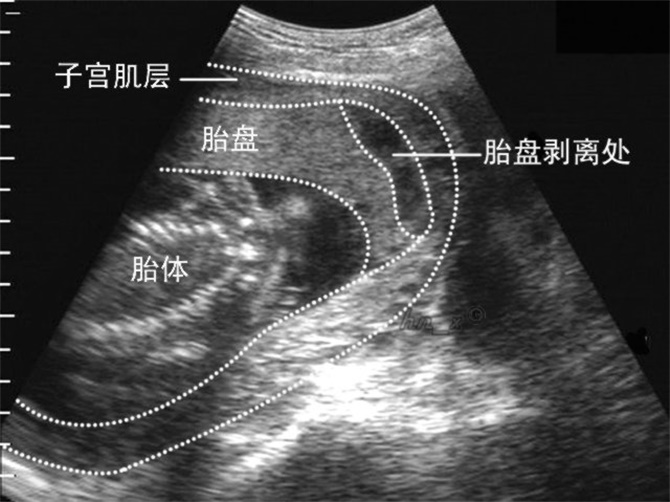

胎盤早剝超聲診斷

胎盤早期剝離